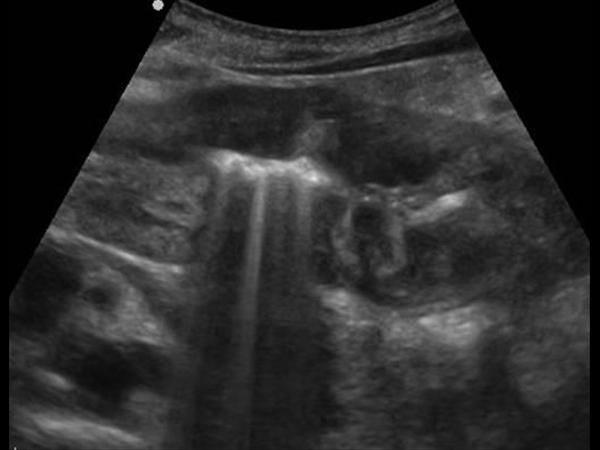

U dạ dày

» Thông tin: Nam giới – 41 tuổi.

» Lâm sàng: Đau thượng vị / Sút cân.